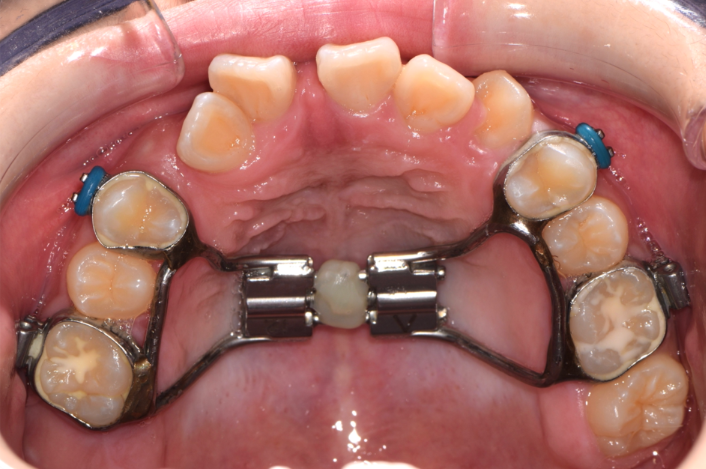

早期牙弓擴張術 (Rapid Maxillary Expansion)

牙弓擴張主要針對上顎進利矯正,透過牙弓矯正裝置裝進上顎牙齒內側,以嘗試撐開上顎的牙弓、擴張空間,慢慢地利用裝置的壓力來把牙弓擴張,讓整個上顎變大,並讓上顎能容納更多牙齒,藉此使牙齒排列回復正常。

上牙弓正常情況下會比下牙弓大,因此在正常咬合的狀態,上顎的牙齒應全都包覆在下顎牙齒的外側。但因基因遺傳、日常生活的壞習慣、因鼻塞長期習慣用口腔呼吸導致很多人牙弓越來越小,導致口腔沒有足夠的空間容納牙齒,因此造成齒列不整、上顎發育不佳,更可能有戽斗狀況產生。

治療前